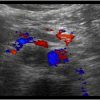

Huyết khối TM chủ dưới

» Thông tin: Nữ giới – 68 tuổi.

» Lâm sàng: Sưng phù chi dưới.